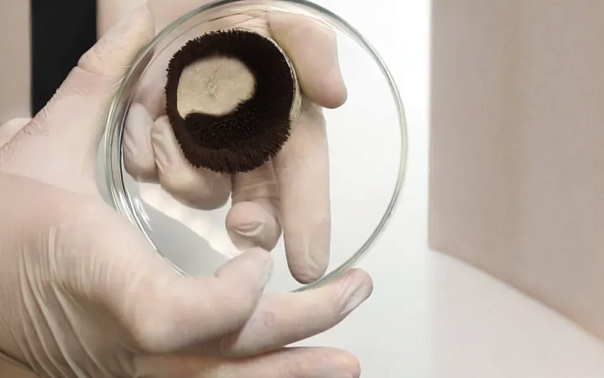

Ученые Пермского Политеха и ПГМУ им. Вагнера впервые за 25 лет зафиксировали в России малоизученную болезнь Пика Ученые Пермского Политеха и ПГМУ им. Вагнера изучили мозг пациентки с симптомами деменции после вскрытия, осуществили анализ клеток и установили болезнь Пика. Задокументированное морфологическое исследование...